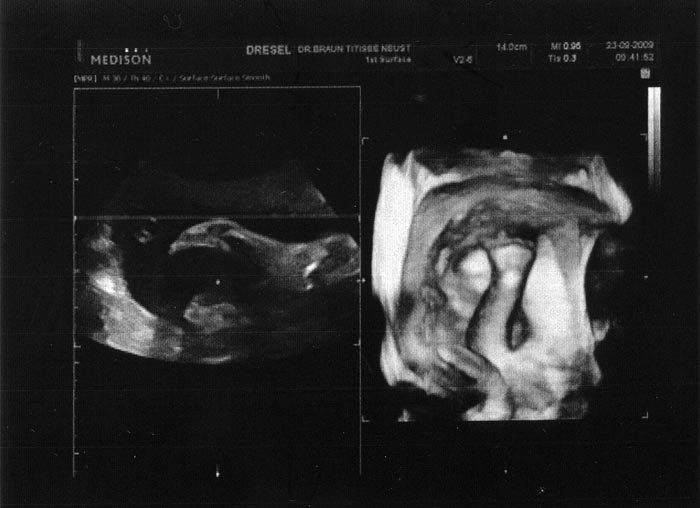

4. Ultraschallaufnahme